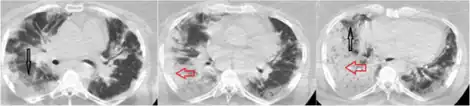

a-f) Chest computed tomography and histologic findings of viral pneumonia | |